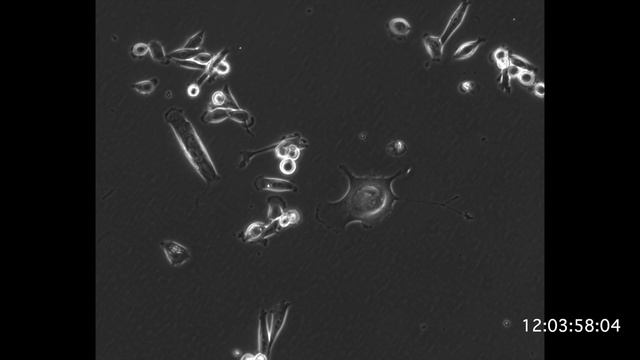

MDA-MB-231 48 hours treatment of Inonotus obliquus смотреть онлайн

00:40

MDA-MB-231 48 hours treatment of Inonotus obliquus

Поиск опенок 16 просмотров